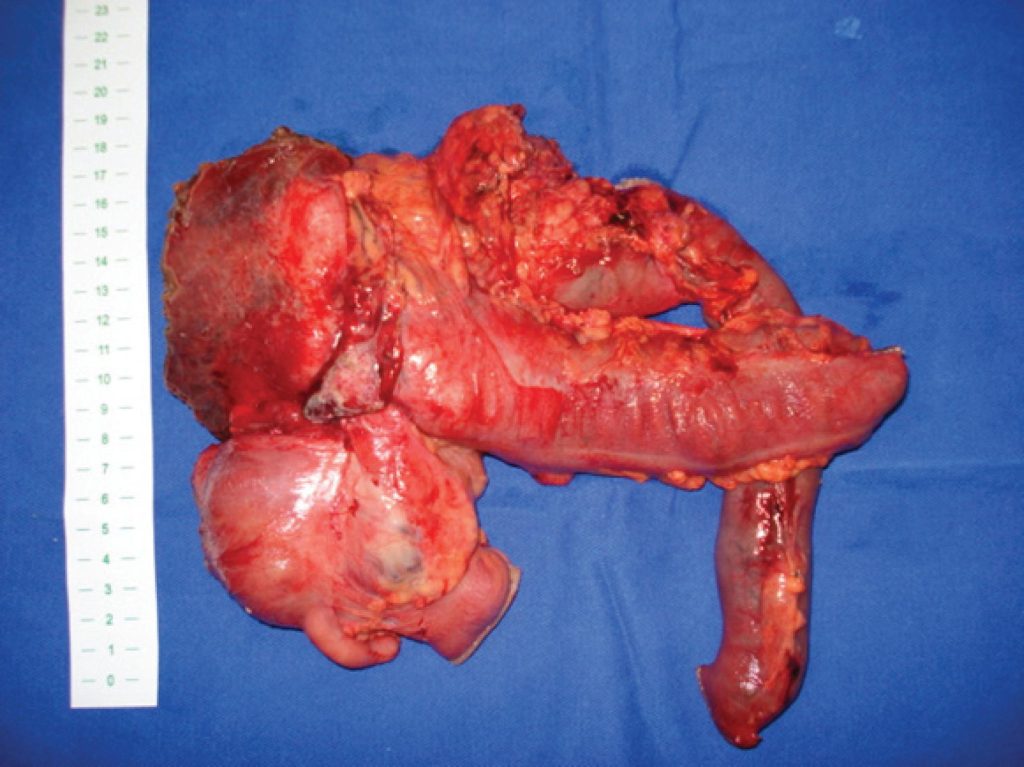

En bloc pancreaticoduodenectomy and right hemicolectomy to treat locally advanced right colon cancer: report of three cases

Although colorectal tumors are fairly common surgical conditions, 5 to 12% of these tumors are locally advanced (T4 tumors) upon diagnosis. In this particular situation, the efficacy of en bloc multivisceral resection has been proven. When right-colon cancer invades the proximal duodenum or even the pancreatic head, a challenging dilemma arises due to complexity of the curative surgical procedure. Therefore, en bloc pancreaticoduodenectomy with right hemicolectomy should be performed to obtain free margins. The present study reports three cases of locally advanced right-colon cancer invading the proximal duodenum. All of these cases underwent successful en bloc pancreaticoduodenectomy plus right hemicolectomy, with no death occurrence. Long-term survival was observed in two cases (30 and 50 months). In the third case, the patient did not present any recurrence twelve months after surgical treatment. Multivisceral resection with en bloc pancreaticoduodenectomy should be considered for patients who present acceptable risk for major surgery and no distant dissemination. This approach seems justified since the length of postoperative survival is longer in radically ressected groups (R0) than in palliativelly resected groups (R1-2).